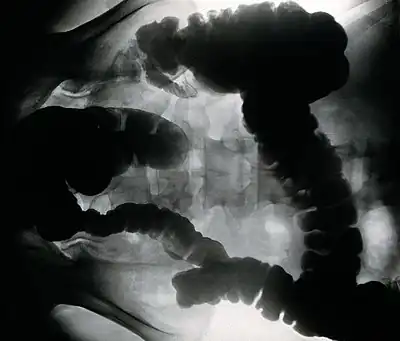

X-ray of colon infected with E. histolytica

Amoebozoa are characterized by the use of pseudopodia for movement and feeding. These protists reproduce by binary or multiple fission.

Entamoebida lack mitochondria and possess mitosomes. Entamoeba histolytica is a pathogenic parasite known to cause amoebiasis, which is the third leading cause of parasitic deaths.[21] It is diagnosed by the assessment of stool samples.[22] Amoebiasis is caused by the ingestion of food or water contaminated with feces or other bodily wastes of an infected person, which contain cysts, the dormant form of the microbe. These cysts on reaching the terminal ileum region of the gastrointestinal tract give rise to a mass of proliferating cells, the trophozoite form of the parasite, by the process of excystation.[23] Symptoms of this infection include diarrhea with blood and mucus, and can alternate between constipation and remission, abdominal pain, and fever. Symptoms can progress to ameboma, fulminant colitis, toxic megacolon, colonic ulcers, leading to perforation, and abscesses in vital organs like liver, lung, and brain. Amoebiasis can be treated with the administration of anti-amoebic compounds, this often includes the use of Metronidazole, Ornidazole, Chloroquine, Secnidazole, Nitazoxanide and Tinidazole. Tinidazole may be effective in curing children.[24] The usage of conventional therapeutics to treat amoebiasis if often linked with substantial side effects, a threat to the efficacy of these therapeutics, further worsened by the development of drug resistance in the parasite.[21] Amoebic meningoencephalitis and keratitis is a brain-eating amoeba caused by free-living Naeglaria and Acanthomoeba. One way this pathogen can be acquired is by soaking contact lenses in water instead of contact solution. This will result in progressive ulceration of the cornea.[25] This pathogen can be diagnosed by demonstration of amoebae in clinical specimens. There is currently no drug therapy available for amoebic meningoencephalitis and keratitis.